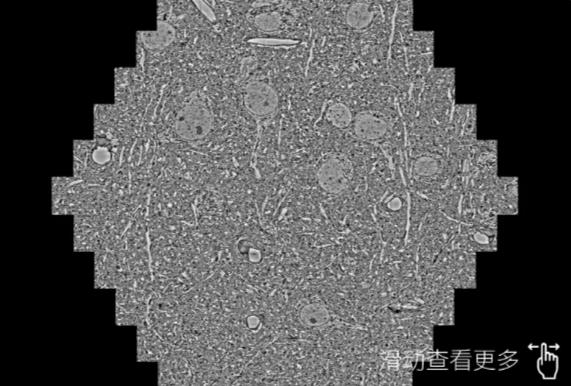

鼠脑切片。左图使用上海蔡司上海扫描电镜MultiSEM706对165μmx143pm面积区域成像,耗时仅需1.5秒。右图为鼠脑切片中30μm区域放大效果。样品由芝加哥大学B.Kasthuri提供。